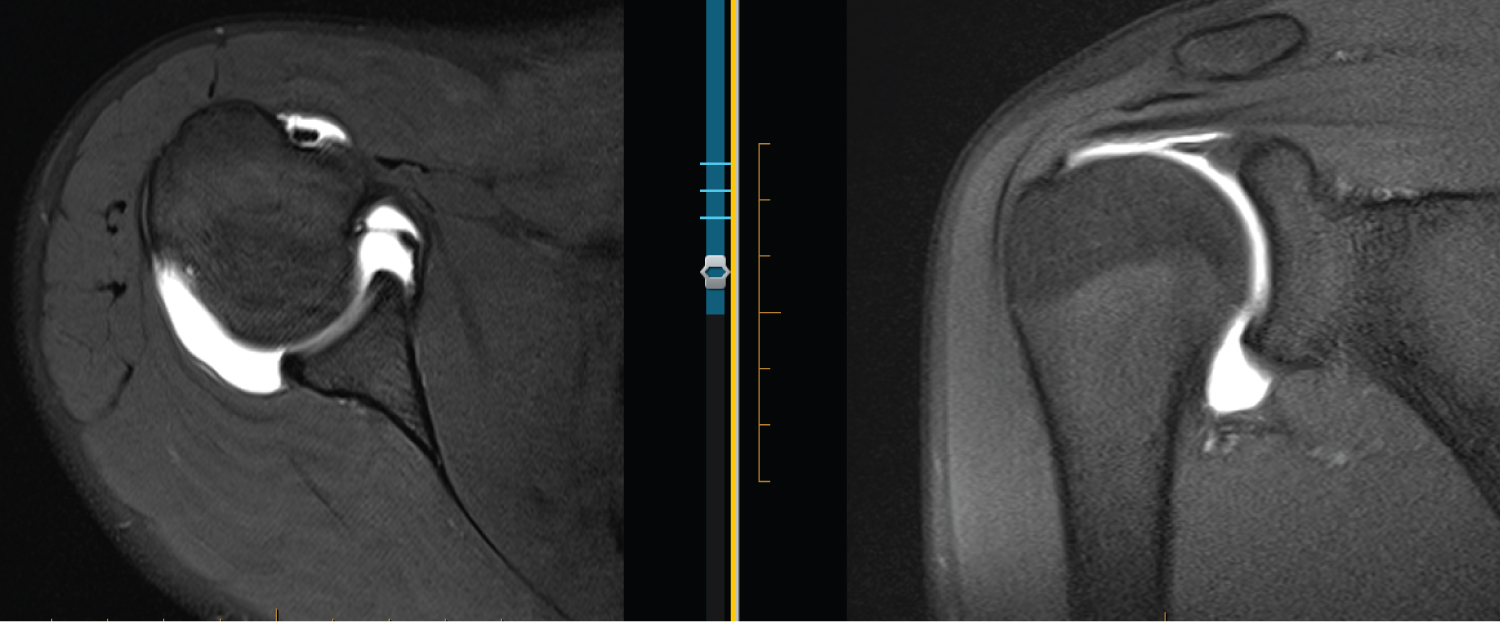

Figure 1: 16 F R MRA. From left to right: Axial T1 FS, Coronal T1 FS, and T1 FS ABER. Labrum looks blunted, rounded and undefined on axial. Nearly absent on coronal. Intact IGHL on ABER and intact labrum. View Figure 1